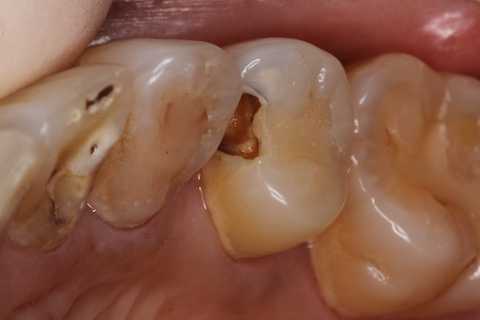

40代女性、左上5、冷水痛+

注意点はCRの接着面は新鮮歯質を確保して歯髄に近いところの軟化象牙質はあまり追求しないでも良い。α-TCPセメントの硬化と接着を妨げない程度に乾燥できれば良い。軟化象牙質は原材料のα-TCPと多少の水分があれば自然に再硬化するようだ。

では時系列でどうぞ